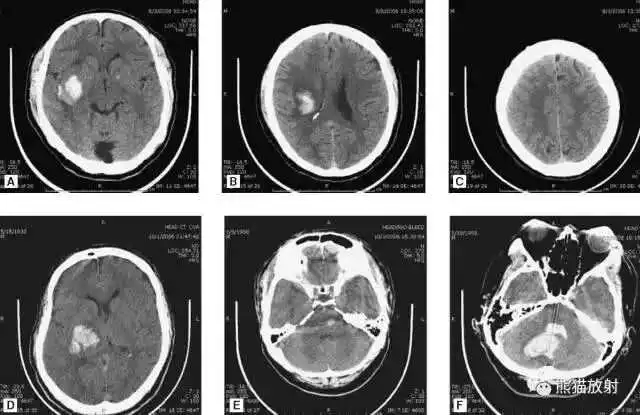

高血压性脑出血:

- 自发性出血;

- 继发于长期高血压及慢性血管病;

- 常见于基底节区、丘脑、脑桥、小脑。

A:占位效应,相邻脑沟、脑池消失;

F:脑出血破入四脑室。

钩回疝:

是当代偿机制不能适应占位性病变时的结果。

基底节区大量高血压性脑出血,破入脑室及蛛网膜下腔,周围水肿,脑干周围空间消失;脑干出血、脑积水。